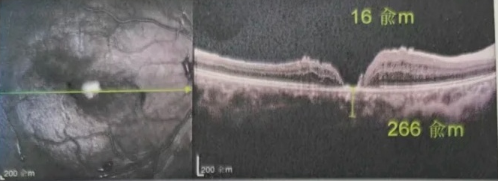

去年年底,年逾7旬的吳爺爺突然發(fā)現右眼看不清,且看東西變形,到當地醫院檢查后確診黃斑裂孔。此后他輾轉求醫,經(jīng)歷了兩次玻切聯(lián)合內界膜剝除術(shù),每次術(shù)后都嚴格“趴睡”一個(gè)月。然而結果令人失望:裂孔不但沒(méi)閉合,反而持續擴大,甚至還并發(fā)高眼壓。

由于自身患有頸椎病,每次術(shù)后長(cháng)期的趴睡都讓他痛苦不堪。為了尋求更好的治療,吳爺爺來(lái)到廈門(mén)大學(xué)附屬廈門(mén)眼科中心,找到了眼外傷及眼底病2科的李海波博士后。此時(shí),吳爺爺右眼的黃斑裂孔已經(jīng)持續擴大到780μm,演變?yōu)殡y治性的大裂孔。

最讓吳爺爺難以置信的是:術(shù)后只需保持平躺24小時(shí)!第二天復查時(shí),眼底鏡及OCT檢查清晰顯示——那個(gè)折磨了他大半年的大裂孔,竟然閉合了!且吳爺爺的右眼視力有了明顯的改善,術(shù)后3天已經(jīng)可以看到 0.15。